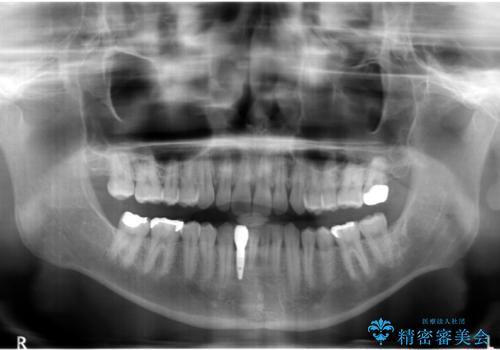

- 下の前歯が1本生まれつき少なかったため、インプラント治療を行いました。

インプラントの前に矯正治療を行い、入れる隙間を確保しました。

被せ物の色を決める前に、ホワイトニングを行なっています。

- 45万円(税別) 内訳:ストローマンインプラント(1本)20万円、ジルコニアクラウン10万円、シリンダーTeC 2万円 ジルコニアカスタムアバットメント10万円 ホワイトニング(エクセレント)3万円費用は治療当時の料金となります

ブリッジにすることも可能でしたが、両側の歯が天然歯であること、また、事前に矯正で噛み合わせを整え、幅も確保していたこと、CTにより骨の厚みがある程度あったことを踏まえ、インプラントも可能であるとお話しし、選んでいただきました。

唇側の骨増成もしっかり行い、前歯部インプラントによくある、歯茎が下がって見えることもない、審美的なインプラント補綴ができました。